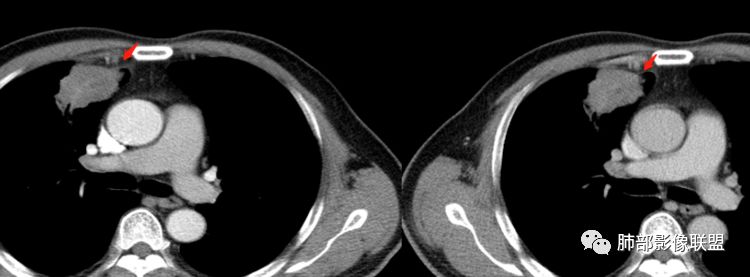

水平裂以上,上叶前段,先看周围,非远端有斑片状高密度影。

边缘平直、稍凹陷,部分区域膨隆。 医学百科网 | YxBaike.Com

宽基底与胸膜相连,附近胸膜稍增厚。

支气管进入病灶内,近端堵塞,断端圆钝。

支气管壁均匀稍增厚。